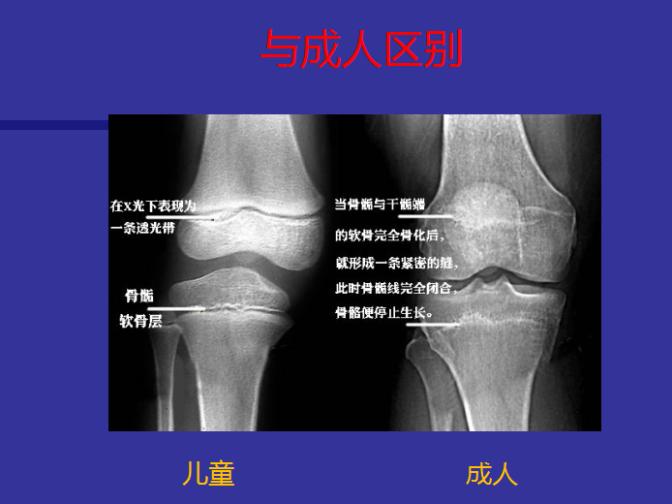

近日,沈阳市骨科医院小儿骨科医生于泓淼来到中国邮政储蓄牛心垛营业所,为辖区百姓讲解"儿童骨骺损伤诊断与治疗"的相关知识。于医生介绍,骨骺损伤是涉及骨骼纵向生长机制损伤总称。包括骨骺、生长板、Ranvier区、与生长相关的关节软骨及干骺端损伤。

儿童骨骺损伤是儿童常见及特有的损伤,约占儿童骨折的三分之一,骨骺的损伤可能带来肢体的变形、不等长等问题。尽管骨骺的损伤会产生较严重的问题,但如果有专业的小儿骨科医生处理得当,其修复的结果往往还是令人满意的,所以骨骺损伤的诊断与治疗决定了预后。